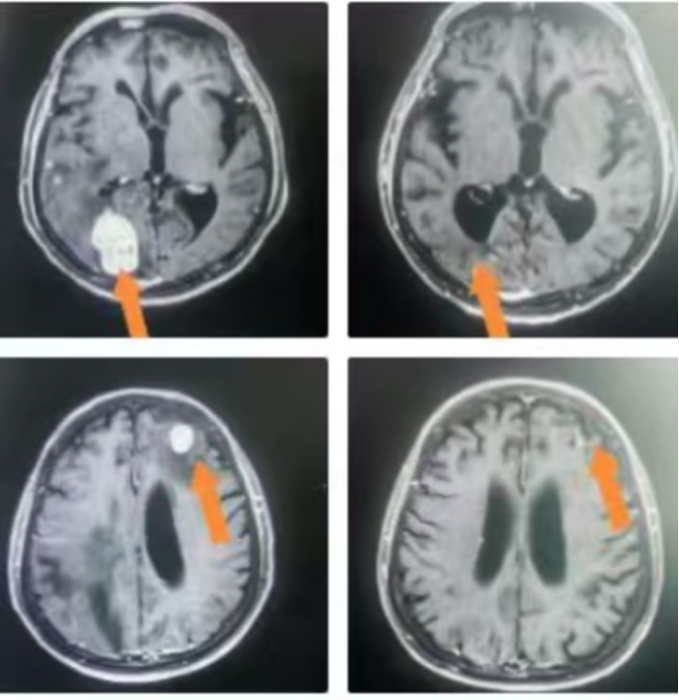

△病例展示

2. 晶格放疗(Lattice Radiation Therapy, LRT):这是GRID疗法的3D进化版。我们在CT模拟定位后,基于患者的个体化肿瘤三维形貌,在治疗计划系统中虚拟设计一个三维的“剂量晶格”,将多个高剂量“球体”精确布设在肿瘤内部,特别是乏氧和增殖活跃的区域。这种“多点聚焦”式的设计,实现了治疗计划的高度个体化、精确化与安全化。

1. 卓越的局部控制率: 对于大体积肿瘤,SFRT展现了惊人的快速消退能力。患者通常在治疗后短期内即可观察到肿瘤体积的显著缩小,症状(如疼痛、压迫)得到迅速缓解。